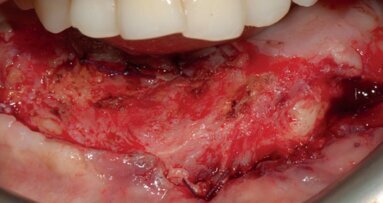

A 36-year-old male patient presented for treatment with advanced, extensive caries and localized periodontal disease (Figs. 1a–c). In addition to not having seen a dentist in more than 20 years, the patient was recovering from an addiction to methamphetamine, which had caused excessive clenching and grinding that had substantially worn down the patient’s teeth. The many years of dental neglect combined with these parafunctional habits to render the patient’s severely decayed dentition untreatable (Fig. 2). Further, the deterioration of the patient’s teeth was accompanied by significant soft-tissue recession and bone resorption.

Because of the patient’s relatively youthful age and his continued bruxing habit, eight implants were proposed for each arch in order to maximise the distribution of occlusal load, the preservation of his ridges, and the long-term prognosis of the restoration. The resorbed state of the patient’s maxillary and mandibular ridges necessitated a grafting procedure to create the foundation needed for implant placement. Custom abutments would be used to position the prostheses for optimal aesthetics. Although BruxZir Solid Zirconia Full-Arch Implant Prostheses (Glidewell Europe GmbH; Frankfurt/Main, Germany) would have been the ideal restorations given the need for long-term durability in this case, the product was not yet available at the time of treatment. Thus, PFM prostheses were chosen in order to avoid acrylic and its susceptibility to staining, wear and fracture. The proposed PFM restorations included layered pink porcelain to recreate the patient’s natural gingival contours. All aspects of treatment were explained to and accepted by the patient. The first phase of treatment began by atraumatically extracting the patient’s entire dentition using Physics Forceps (Golden Dental Solutions Inc.; Detroit, USA), which allowed for removal of the teeth without causing any damage to the surrounding bone. The extraction sockets were filled with grafting material in order to preserve the sockets and rebuild the maxillary and mandibular ridges for ideal implant placement. The patient was provided with immediate dentures, which were prefabricated based on impressions that were taken at a previous appointment (Fig. 3).